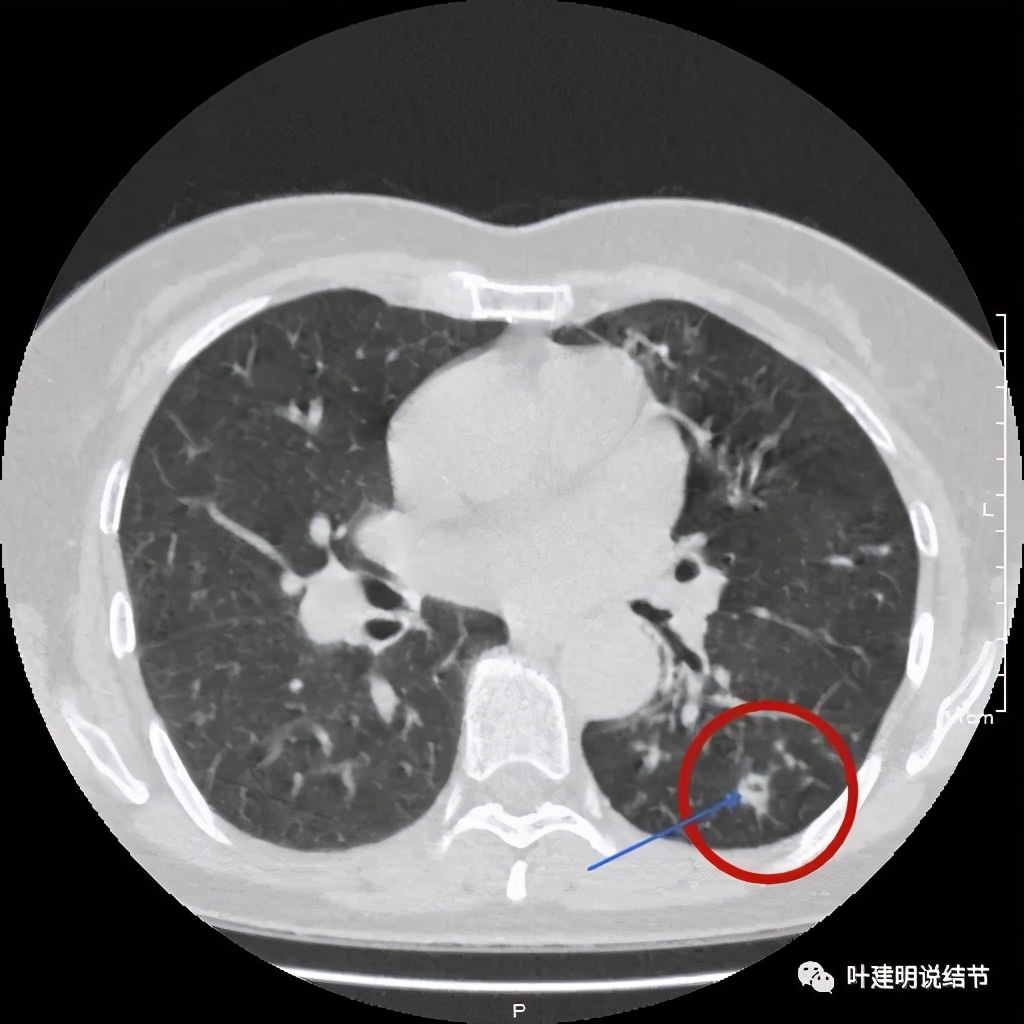

上图见病灶边上有血管

上图示病灶血管征较明显,有微小血管从不同方向走向病灶

其实若从以上影像上看,恶性还真不能除外的,相对来说,恶性的可能应该大于良性。但看肺结节,我们在看细节特征的同时,还要看其他肺野有没有异常,综合来考虑。因为她的左下肺其他部位有病变存在,先来看下图像: